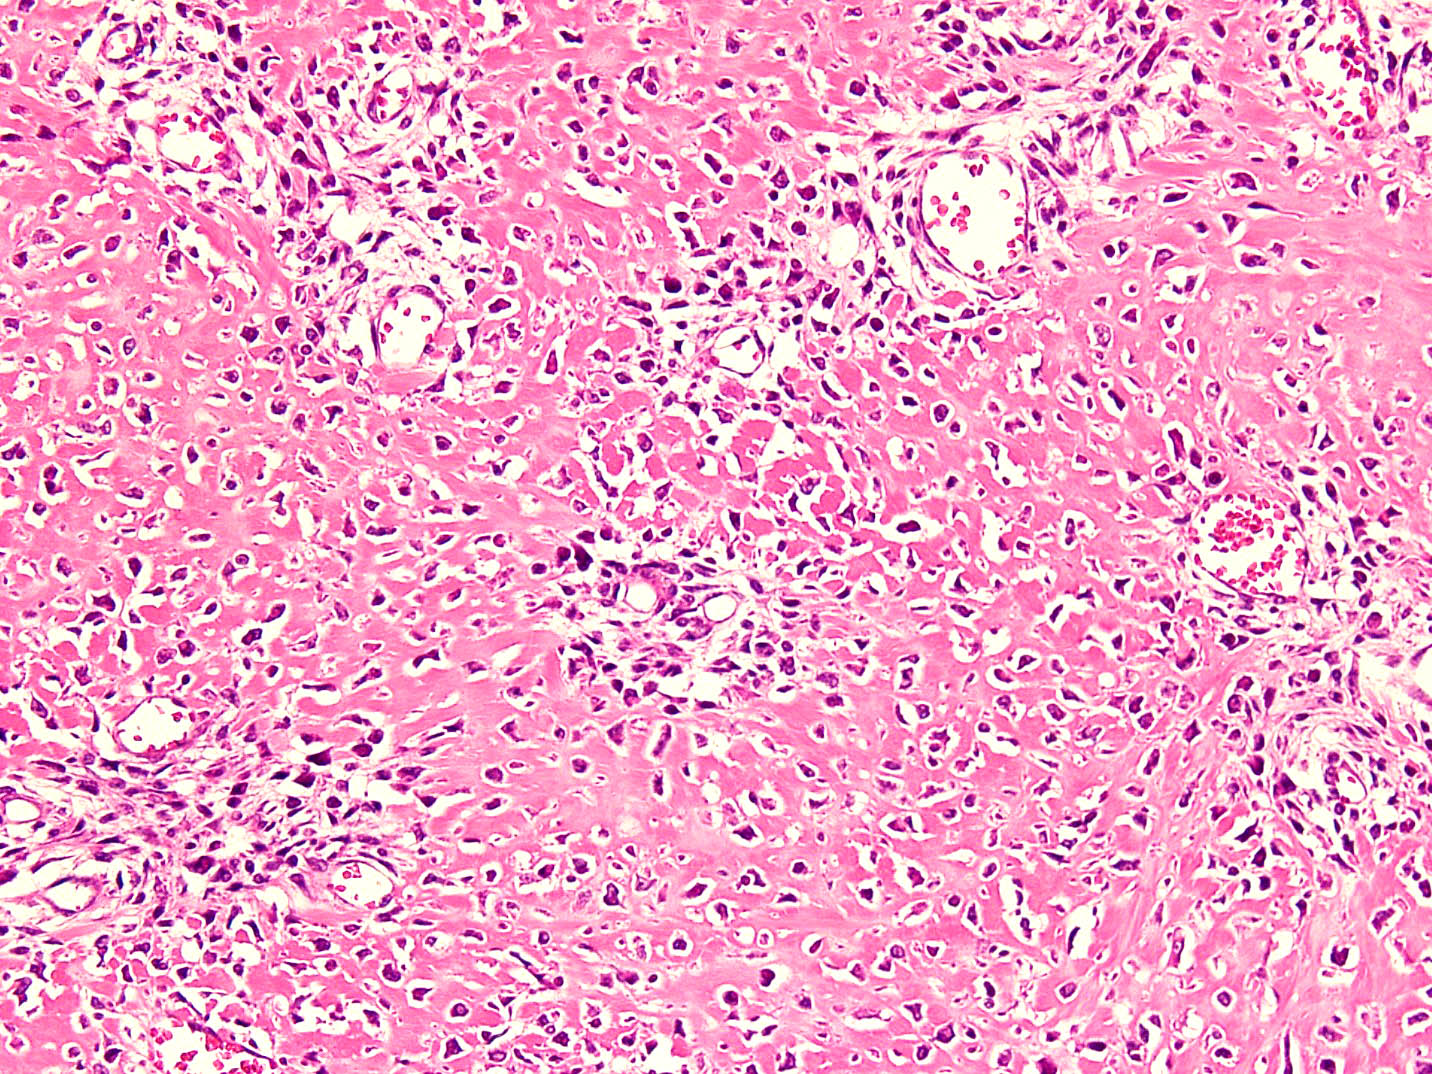

- Histologically, zonal pattern is characteristic with different degrees of cellular differentiation (inner zone, intermediate zone and peripheral zone)

- Inner central zone:

- Composed of fibroblastic / myofibroblastic proliferation, which is richly vascular, rich in inflammatory cells and resembles nodular fasciitis; some multinucleated giant cells may also be seen

- Cells show mild degree of pleomorphism and brisk mitosis

- Areas of hemorrhage, fibrin, endothelial proliferation and entrapped atrophic muscle fibers are noted

Microscopic (histologic) images

A 36 year old boxer presented with a painful mass in the right arm for the last 1.5 months. On radiology, an intramuscular mass was seen with peripheral mineralization and central latency. It was biopsied, which showed the morphology in the image above. What is the most likely diagnosis?

B. Myositis ossificans. The given history in this case shows that the patient is physically active and provides short duration history of the lesion. The radiological findings suggest a lesion with maturation at periphery. The microscopic image shows characteristic zonation. These are all features of myositis ossificans.